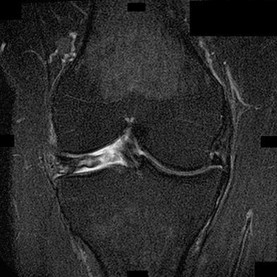

A 22-year-old man sustains an injury to his right knee in a motor vehicle collision. Figure 22a is the posterior stress radiograph of the involved knee, and Figure 22b is a selected MR image that identifies the injured structure.

CLINICAL SITUATION FOR QUESTIONS 22 THROUGH 25

The stress radiographs demonstrate posterior instability of the right knee in flexion. The MR images demonstrate injury to both the anterior and posterior cruciate ligament (PCL), with the stump identified with the arrow on the MR image (Figure 22b). The PCL has 2 functional bands. The anterolateral bundle originates from the roof of the intercondylar notch. It runs in a posterolateral direction onto the tibial crest between the posterior attachment of the medial and lateral menisci. During a double-bundled posterior ligament reconstruction, the

anterolateral bundle is tensioned with the knee in a position of mid flexion. The posteromedial bundle has a variable pattern of tension both in extension and in high flexion. Tensioning of the posteromedial bundle in extension may contribute to resistance against knee hyperextension.

The meniscofemoral ligaments are variably present. Although 93% of knees have been reported to have at least 1 meniscofemoral ligament present, both ligaments are simultaneously present in approximately 50% of knees. The ligament of Humphrey (anterior meniscofemoral ligament) and ligament of Wrisberg (posterior meniscofemoral ligament) are delineated by their anatomic relationship to the posterior cruciate.